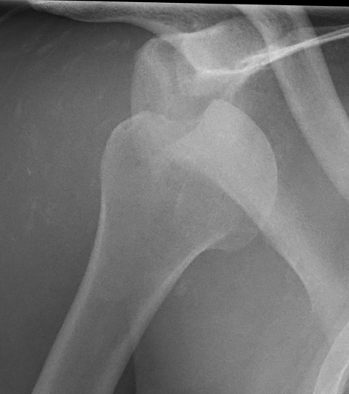

Engaging Hill Sachs

Incidence

Yiannakopoulos et al Arthroscopy 2007

- 127 shoulder dislocations

- 88% Hill Sachs

Measurement Hill Sachs

Best fit circle of the articular surface of humeral head

Measure percentage involvement of articular surface

Hill Sachs 30% of the articular surface

Hill Sachs 25% of the articular surface